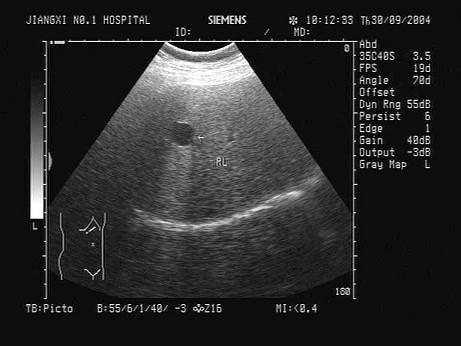

问题 根据肝脏声像图表现,诊断为?(?)

选项 A.转移性肝癌 B.肝血管瘤 C.肝脓肿 D.肝囊肿 E.肝内胆管囊状扩张

答案 D